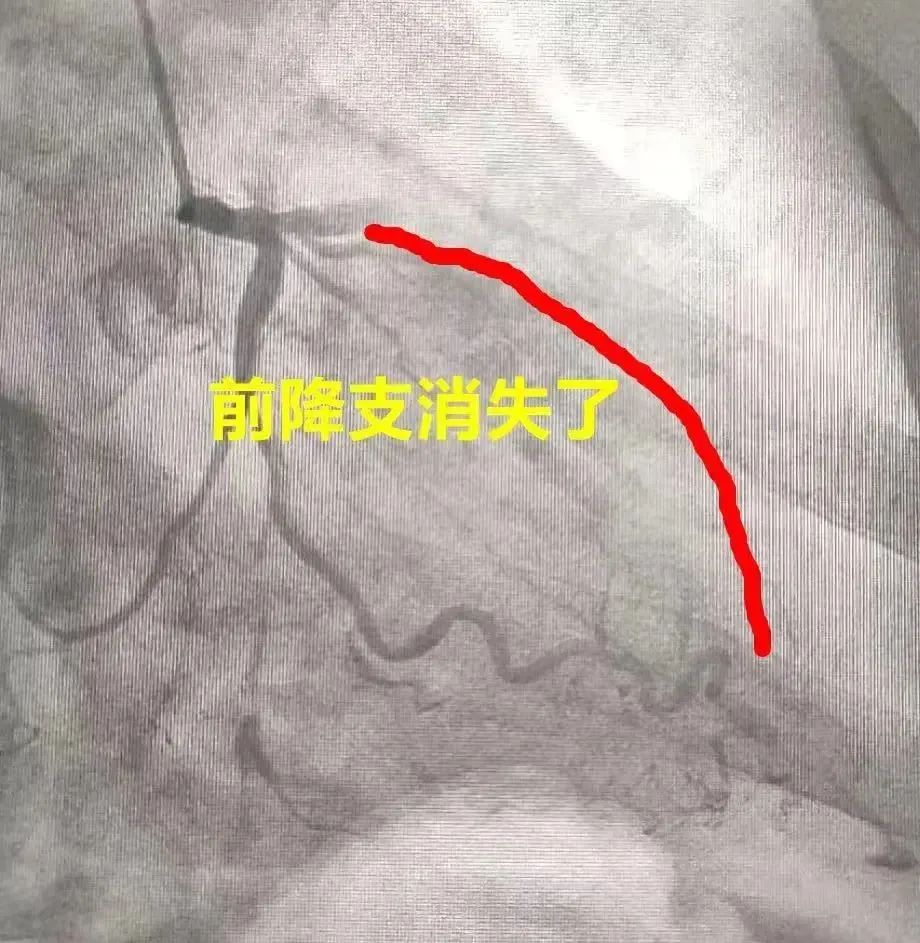

不久之前 深圳下班高峰 地鐵一乘客突然暈倒! 當時,因為情況緊急 當事人反復(fù)暈暈醒醒 大家沒法細究他倒下的原因 直到送去醫(yī)院 才確定,是—— 急 性 心 梗 坐地鐵爆發(fā)第3次心梗 10分鐘連暈2次 據(jù)深圳衛(wèi)健委消息,這位暈倒的乘客,是一位姓劉的大叔,今年67歲。 事發(fā)經(jīng)過 據(jù)悉,事發(fā)那天是傍晚6點多。劉大叔在車廂里突然暈倒,同行家屬見狀,急忙往他嘴里塞了一顆速效救心丸。 車站工作人員趕到現(xiàn)場后,當即把劉大叔攙扶下車,并開始搶救。幾分鐘后,人醒了,但約7分鐘后又暈了,過了1分鐘又恢復(fù)意識。 工作人員便一邊叫120,一邊繼續(xù)搶救,并提前扛來AED以備萬一。 入院后確診 10多分鐘后,劉大叔被送到深圳市人民醫(yī)院。經(jīng)胸痛中心綠色通道入院后,發(fā)現(xiàn)他這回——3個心臟大血管,堵了兩個。 圖源:深圳衛(wèi)健委 據(jù)深圳衛(wèi)健委解釋,當年劉大叔確診冠心病時,它們已有堵塞,但一直沒好好處理,直到現(xiàn)在倆血管“垃圾”越積越多——劉大叔爆發(fā)第3次心梗,梗到他當場暈厥。 深圳市人民醫(yī)院心內(nèi)科副主任醫(yī)師 梁新劍表示—— “很多支架患者就是這樣,最初都能遵醫(yī)囑控制病情,過了段時間感覺自己哪都挺好,就開始停藥、熬夜、也不鍛煉了。 但其實,支架是治療的開始而不是結(jié)束,否則還是你的血管扛下所有! 最后,心內(nèi)科團隊給劉大叔的右冠狀動脈和左回旋支狹窄處分別放了支架。至此,他身上已有4個支架。 3年前 心“死了一大半!” 據(jù)深圳衛(wèi)健委消息,乘客劉大叔在3年前,因胸悶入院,發(fā)現(xiàn)自己的左前降支近中段99%狹窄了。 醫(yī)學(xué)示意(來源:網(wǎng)絡(luò)) 這意味著——他的心臟,一大半快要“死”了。 因為這根血管又粗又大,承擔心臟7-8成供血量,一旦堵塞,會導(dǎo)致大面積心梗,特別容易誘發(fā)猝死。 很多30-50歲的青壯年男性,就是這樣沒命,他們的伴侶由此變成寡婦。 所以,這血管也被稱作“寡婦血管”。 圖源:深圳衛(wèi)健委 讓人意想不到的是 這次在地鐵站內(nèi)暈倒 已經(jīng)是他3年里 第3次栽倒 而這背后 就是這個“寡婦團”在作怪—— 心臟血管 “三姐妹 ” 圖源:深圳衛(wèi)健委 幾種“心大”的男人 是奪命“寡婦”最愛 作為冠心病的一種,“寡婦血管”病約占發(fā)病總數(shù)的5%,不怎注意生活習(xí)慣的中青年男性,特別容易中招: ☞ 高血壓 ☞ 糖尿病 ☞ 吸煙 ☞ 家族有冠心病史 上文提到的劉大叔就是有10多年的高血壓、5年糖尿病、30多年吸煙史,最后確診的。 所以,當時劉大叔在體內(nèi)裝了個支架?蓻]過半年,他又“!绷耍蚴術(shù)后不規(guī)律服藥。他只好又在原來的支架上再套一個支架。但沒過多久,又松懈了,直到發(fā)生前不久的意外...... 通常其他冠心病發(fā)作時,血管堵了90%以上才考慮開通,但以左前降支為代表的左主干動脈,堵50%就已經(jīng)很嚴重了。 圖源:@心血管內(nèi)科侯曉平 有些心梗不會“喊痛” 特別是這2種人! 對心梗來說 最常見的癥狀是—— 胸骨后壓榨樣疼痛 如果你突然感覺胸痛胸悶、出汗,而且一陣一陣地痛,像胸前壓著一塊大石頭、被死死鉗住,有一種快死掉的感覺...像下圖這樣—— 來源:騰訊醫(yī)典 發(fā)現(xiàn)上面所說的癥狀,要警惕!很可能是心絞痛,但對有些人來說,心梗卻不會“喊痛”: ☞ 老年人 ☞ 糖尿病患者 因為他們痛覺神經(jīng)不敏感,或心梗范圍比較小,可以不表現(xiàn)為胸痛,但會以意識喪失為首要表現(xiàn)。 據(jù)深圳市人民醫(yī)院心內(nèi)科副主任醫(yī)師 梁新劍表示—— “像劉大叔一樣,心梗發(fā)生后暈倒,可能是因為心臟泵血功能下降,血壓偏低,引起腦供血不足;同時,心梗后心率變慢,甚至出現(xiàn)嚴重的傳導(dǎo)阻滯或心動過緩、腦缺血缺氧,輕者頭暈、有昏沉感,嚴重可出現(xiàn)意識喪失,甚至猝死! 這種時候 千萬別大意 趕緊去醫(yī)院! 治療過程中還要 遵醫(yī)囑,正規(guī)治療 這些心梗癥狀很少人知道 ☞ 腹痛,特別是上腹痛,個別人是腹股溝附近痛; ☞ 牙痛、下頜痛,休息后可緩解,疼痛時可出汗,面色蒼白、瀕死感,服用止痛藥不緩解; ☞ 氣促或呼吸困難,特別是老年人,容易誤以為是呼吸系統(tǒng)疾病。 ☞ 肢體疼痛麻木,個別人是上肢疼痛乏力。